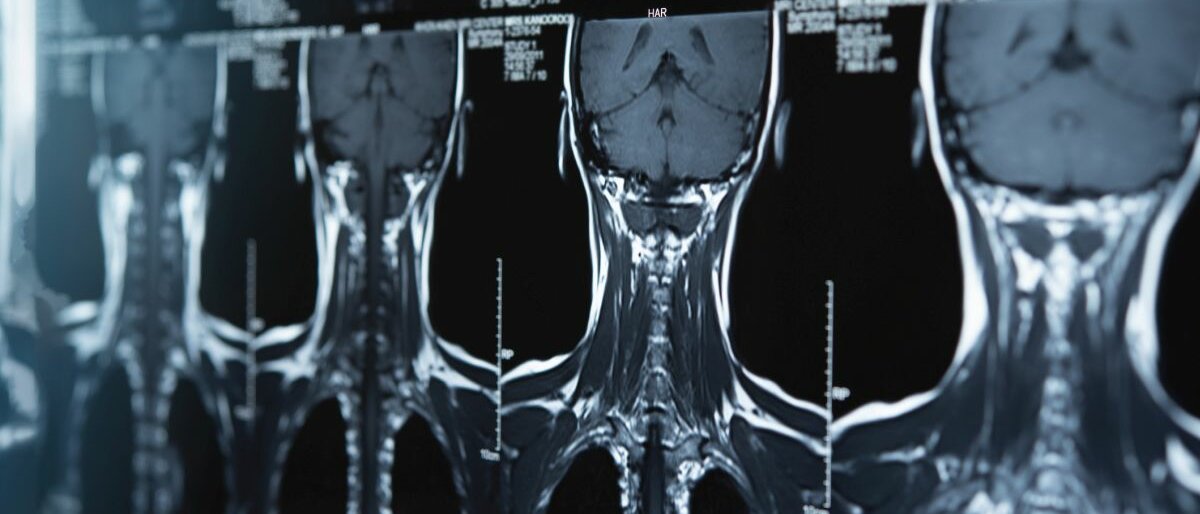

Aus der Medizin sind bildgebende Verfahren wie Röntgen, CT oder Ultraschall nicht wegzudenken. Sie machen sichtbar, was von außen für Ärztinnen und Ärzte nicht zu sehen ist. Bänderrisse, Tumore oder der Zustand bestimmter Gefäße zum Beispiel. Doch es gibt unter Patienten immer wieder auch Vorbehalte gegen die Verfahren, vor allem wegen möglicher Strahlenbelastung.

Es ist die Technik, mit der 1895 erstmals Strukturen im Körperinneren sichtbar gemacht werden konnten. Auch heute spielt sie eine wichtige Rolle bei der Diagnostik von Knochenbrüchen und Lungenerkrankungen. Eine Weiterentwicklung des Röntgens ist die Computertomographie (CT), die Objekte durch Schichtaufnahmen auch dreidimensional darstellen kann. Verbreitet sind zudem der Ultraschall (Sonographie) und die Magnetresonanztomographie (MRT). Diese beiden kommen ohne Strahlenbelastung für den Patienten aus.

Die Radiologie arbeitet mit unterschiedlichen Arten von Wellen. „So sehen wir die unterschiedlichen Kontraste im Bild“, erläutert Prof. Heinz-Peter Schlemmer, Direktor der Abteilung Radiologie am Deutschen Krebsforschungszentrum in Heidelberg. Beim Ultraschall sind es Schallwellen, das MRT funktioniert mit elektromagnetischen Feldern und Radiowellen.